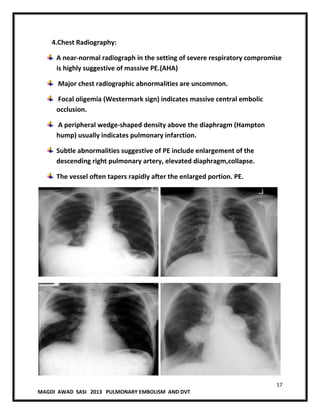

4.Chest Radiography:

A near-normal radiograph in the setting of severe respiratory compromise

is highly suggestive of massive PE.(AHA)

Major chest radiographic abnormalities are uncommon.

Focal oligemia (Westermark sign) indicates massive central embolic

occlusion.

A peripheral wedge-shaped density above the diaphragm (Hampton

hump) usually indicates pulmonary infarction.

Subtle abnormalities suggestive of PE include enlargement of the

descending right pulmonary artery, elevated diaphragm,collapse.

The vessel often tapers rapidly after the enlarged portion. PE.